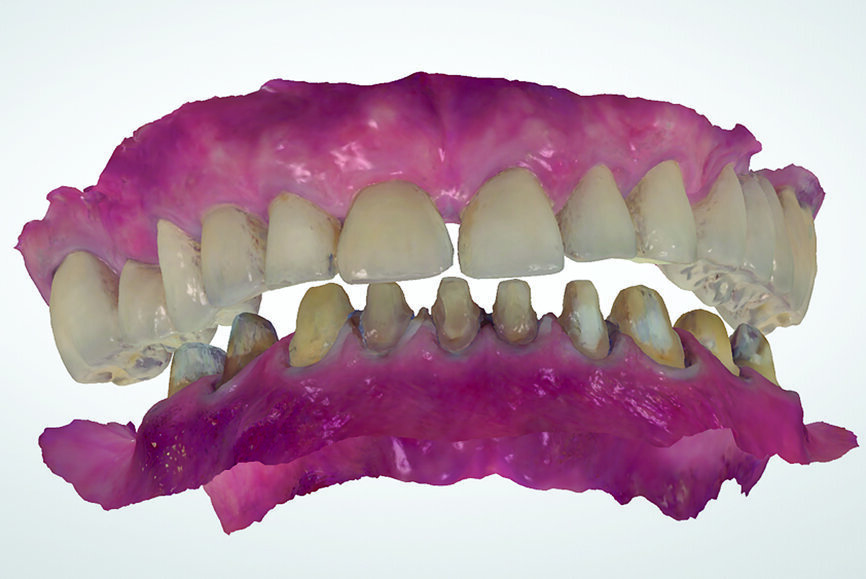

In contrast, digital recording has several advantages regarding efficiency and accuracy. The recording takes place without an interposed medium. The uploading of the digital casts in the software to the IC or CR position happens without the need for positioning of physical stone casts by an operator (technician). This ensures an accurate and efficient mounting in the virtual articulator. The direct digital occlusal recording is based on the intra-oral scanner software matching the digital casts of the arches to the inter-arch scan obtained from the side view of the arches (Fig. 18). The only noted disadvantage of the direct digital recording relates to the additional cost of acquiring an intra-oral scanner and the learning curve associated with operating one.

When the dentist decides to maintain the existing bite, that is, to work with what is there, the focus should be on ensuring that there is no unwanted change in the recording and transmission to the laboratory. Analogue recordings of existing IC can be performed using polyvinylsiloxane registration pastes or waxes (Fig. 19). Dental laboratories usually digitise the analogue records and fabricate the restorations digitally. The process of digitisation can introduce imprecisions, owing to the difficulty of the laboratory articulating the models in the precise position. Digital recordings of existing IC can be performed using intra-oral scanners. The scanner is placed in the buccal corridor and records the relative position of the maxillary and mandibular teeth (Figs. 20a & b).